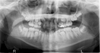

What is wrong with this image?

too far forward

double real image of cervical spine (superimposed on ramus)